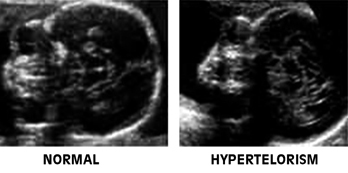

Εικόνα 30. Υποτελορισμός και σύγκριση με το φυσιολογικό, σε εγκάρσιες τομές του κρανίου στο ύψος των οφθαλμικών κόγχων. Εικόνα 31. Υπερτελορισμός, σε σύγκριση με το φυσιολογικό σε εγκάρσιες τομές.

Υπερτελορισμός

Γενικά: Ατελής μετακίνηση των οφθαλμών από τα πλάγια του προσώπου, όπου σχηματίζονται προς τη σωστή τους θέση κοντά στη μέση γραμμή, με αποτέλεσμα αυξημένη διακογχική απόσταση.(6)

Αίτια:

- Σπάνια πρωτοπαθής.

- Συνήθως δευτεροπαθής, ως αποτέλεσμα πρόσθιας εγκεφαλοκήλης ή άλλων ανωμαλιών του προσώπου.

ECHO - ευρήματα στο 2ο τρίμηνο:

- Αυξημένη διακογχική απόσταση.

- Πρόσθια εγκεφαλοκήλη.(27,32)

Υποτελορισμός

Γενικά: Μειωμένη διακογχική απόσταση, κυρίως ορατή στο υπερηχογράφημα 2ου τριμήνου. Συνήθως συνυπάρχει ολοπροσεγκεφαλία.(27,32)

- Μεμονωμένα περιστατικά.

- Στο πλαίσιο γενετικού συνδρόμου (π.χ. τρισωμία 21, Meckel-Gruber).

- Μειωμένη διακογχική απόσταση (μέτρηση έσω με έσω κανθό).